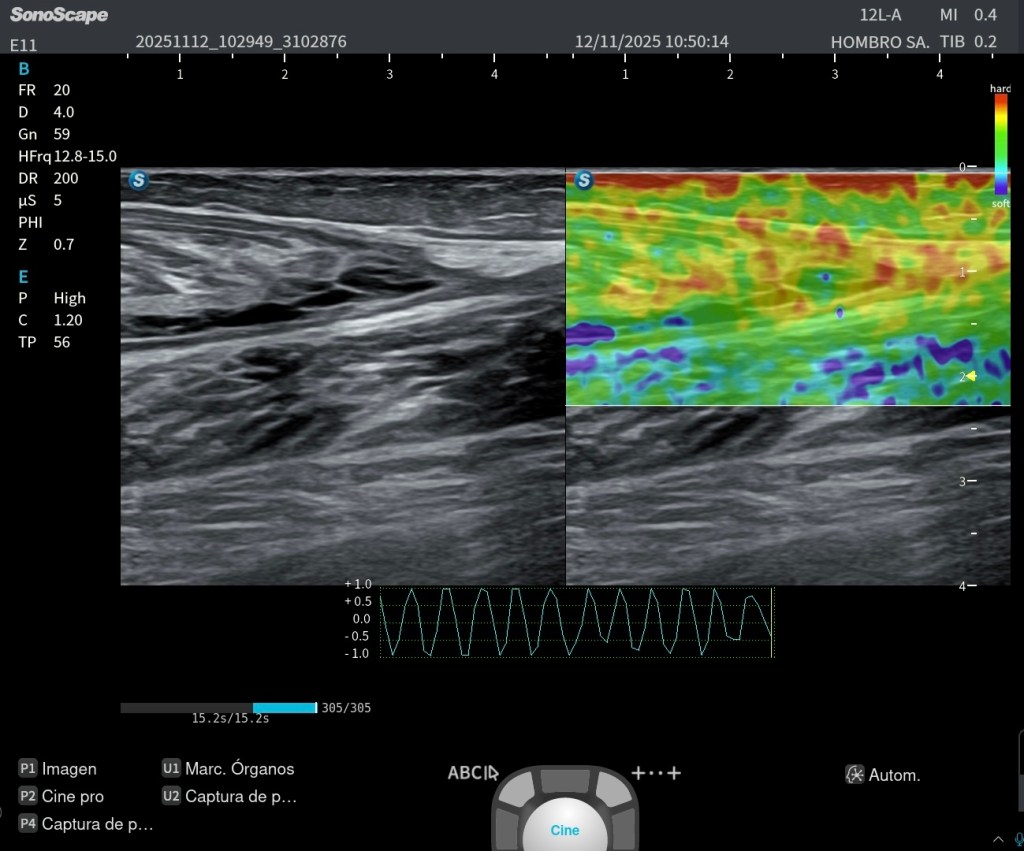

En esta imagen 1 se aprecia de forma muy clara la anatomía en un corte axial oblicuo del tercio medio del cuello anterolateral, una de las ventanas más útiles para el estudio ecográfico del plexo braquial.

En la porción medial identificamos el paquete vascular principal, formado por la arteria carótida y la vena yugular interna, que actúan como referencias anatómicas fundamentales. En un plano más superficial se observa el músculo esternocleidomastoideo, y aún más superficial, el músculo platisma.

Por debajo del esternocleidomastoideo y desplazándonos hacia lateral, aparece el músculo escaleno anterior, que constituye uno de los límites del espacio interescalénico.

Entre el escaleno anterior (medial) y el escaleno medio (lateral) se localiza el plexo braquial, en este nivel formado fundamentalmente por raíces y troncos, no por ramas terminales. Estas estructuras nerviosas presentan en ecografía un aspecto característico, ligeramente hipoecoico, con patrón fascicular, a menudo descrito como “racimo de uvas”.

Más lateral se identifica el músculo escaleno medio, y posteriormente el escaleno posterior, completando el grupo muscular profundo del cuello en esta región.

En el plano más profundo y lateral, se puede reconocer la primera costilla, que actúa como referencia anatómica clave y como límite posterior del espacio donde discurre el plexo.